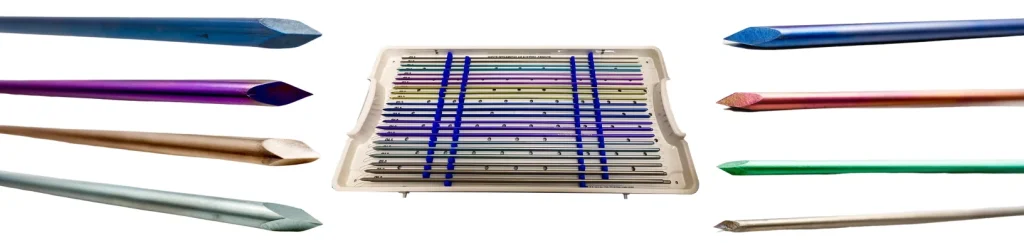

Hastes intramedular Flexível Diamantada

Haste Flexível Diamantada:

Diâmetro: 1,5 – 2,0 – 2,5 – 3,0 – 3,5 – 4,0 – 4,5 e 5,0 mm

Comprimento: 100 – 150 – 300 e 450 mm

Mini Haste Flexível Diamantada:

Diâmetro: 1,0 – 1,2 e 1,4 mm

Comprimento: 100 – 150 e 300 mm

Fabricado com liga de Titânio conforme ASTM F136